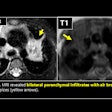

Hammou was a past president of the Mediterranean and African Society of Ultrasound. Her research interests included radiation protection and patient safety, pediatric radiology, and ultrasound.